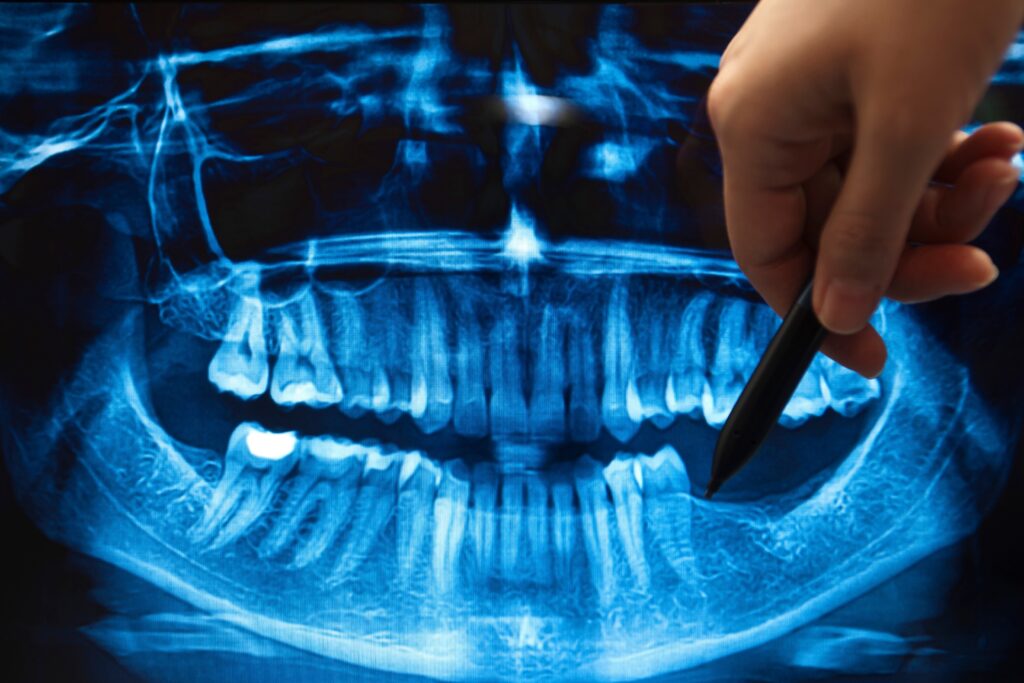

In some cases, a bone graft is placed at the same time as a tooth extraction to preserve the socket and prevent bone loss before it starts. Dr. Koman will evaluate your bone density with 3D imaging during your consultation and let you know whether grafting is needed as part of your implant plan.

Dr. Koman takes 3D imaging to assess the extent of bone loss and determine the type, volume, and placement of graft material needed to support your implant plan.

A successful implant starts with solid bone. Dr. Koman uses 3D imaging to assess every case thoroughly and selects the right grafting approach to give your implant the strongest possible foundation from day one.